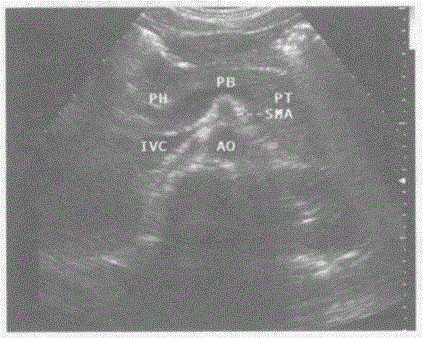

问题 请回答下图及彩图声像图中1、2、3所指部位的解剖名称: {图1}

选项 A.1-脾静脉、2-下腔静脉、3-腹主动脉 B.1-门静脉、2-下腔静脉、3-腹主动脉 C.1-脾静脉、2-右肾静脉、3-腹主动脉 D.1-脾静脉、2-下腔静脉、3-肠系膜上动脉

答案 A